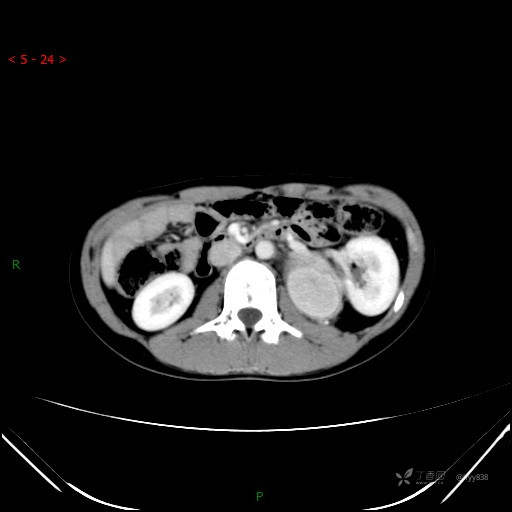

增强静脉期